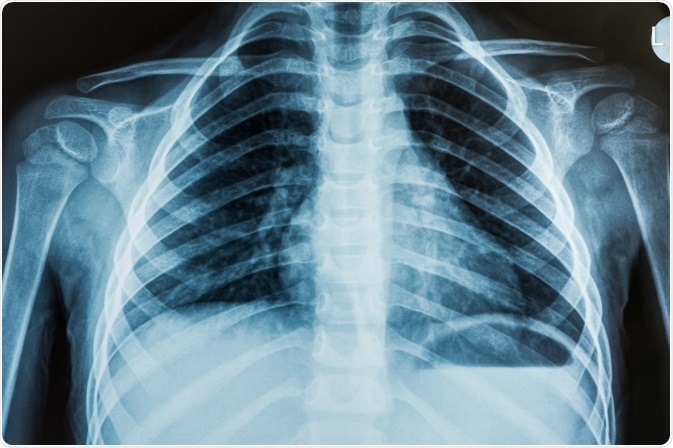

Chest X-ray of patient being tested for ARDSARDS can be diagnosed using a chest X-ray. Image Credit: OZMedia / Shutterstock

This scoring system looks at measures of pressure in the lung, specifically positive end-expiratory pressure and ratio of partial pressure of arterial oxygen to the fraction of inspired oxygen, the compliance of the lung and the degree of infiltration as seen by radiographs of the chest.